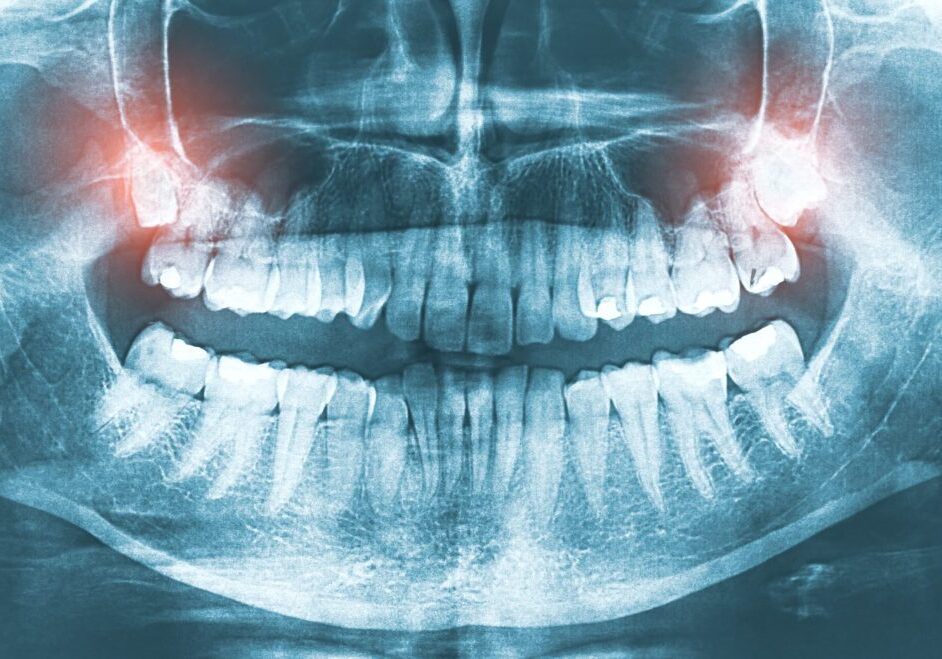

Dental X-Rays

Modern digital X-rays provide a safe, in-depth look at the structures of the teeth and jawbone. They are a vital part of preventive care, allowing Dr. Parsons to detect hidden cavities between the teeth, monitor how adult teeth are developing, and evaluate the position of wisdom teeth before they cause crowding.